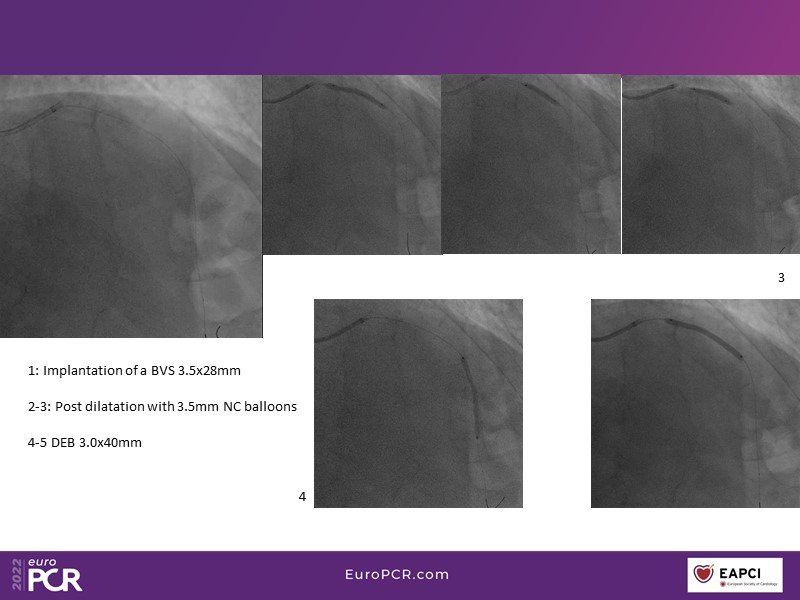

This EuroPCR 2022 session aims to show, based on real-life cases, that even complex coronary disease can be treated without the need for permanent coronary stents. Learn how to prepare the vessel, deliver the therapy, and assess immediate outcomes after "DCB-alone" PCI, discuss de novo, small vessels, and in-stent restenosis cases with follow-up, define what may be an optimal long-term result, refresh the scientific bases, and understand the clinical benefits and safety of paclitaxel DCBs.

- To know how to prepare the vessel, deliver the therapy and evaluate the immediate results after "DCB-alone" PCI

- To discuss de novo, small vessels and in-stent restenosis cases with follow-up and define what may be an optimal long-term result